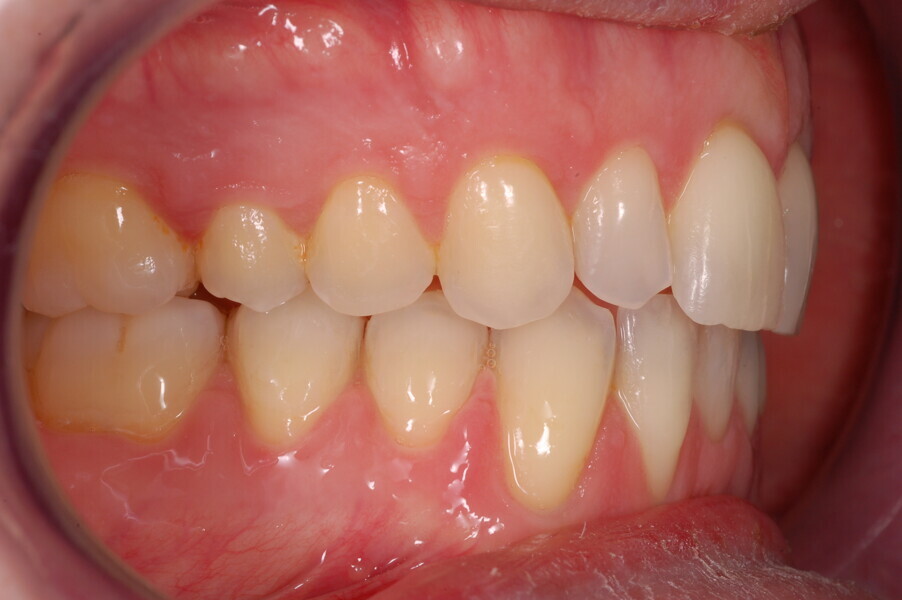

A healthy 39-year-old man presented to our orthodontic office with the chief complaint of an unattractive dental appearance and fear of the orthognathic surgery proposed by another orthodontist. Clinically, the patient’s profile was straight, and the frontal view did not show any facial asymmetry. The functional examination did not reveal any mandibular deviation or reduced movements. The patient had no joint pain, and no joint noise was observed.

Figs. 1–8: Pretreatment facial and intra-oral photographs.

From the periodontal point of view, the patient showed a good attitude to oral hygiene, but crowding of the mandibular incisors made cleaning difficult in that area, causing plaque accumulation and localised gingival inflammation. The panoramic radiograph revealed the presence of the mandibular third molars and confirmed the absence of the mandibular right central incisor (Fig. 10).

The cephalometric analysis showed a skeletal Class II malocclusion (convexity of Point A: 4.9 mm), a slightly retruded chin position (facial depth: 78.1°) and a skeletal open bite tendency (lower facial height: 53.19°; facial axis: 80.58°; Fig. 9). The mandibular incisors were lingually tipped (Li–APog: 9.3°) and retruded (Li–APog: 1.55 mm), and there was an increased inter-incisal angle of 142.9°.